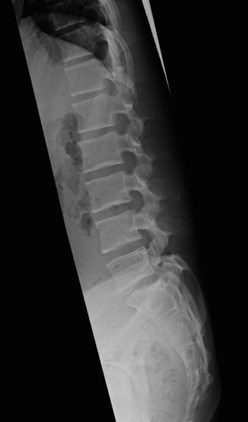

經過基本的評估後,我覺得他除了腰部肌肉僵硬之外,腰部的曲線也不太正常,便讓他照了張X光,結果顯示腰椎的生理曲線確實變得相當平直!於是在經過治療緩解症狀之後,我要小選手務必請家長在下次就診時,一同來醫院了解狀況。

圖片來源:Dr.KP王凱平醫師